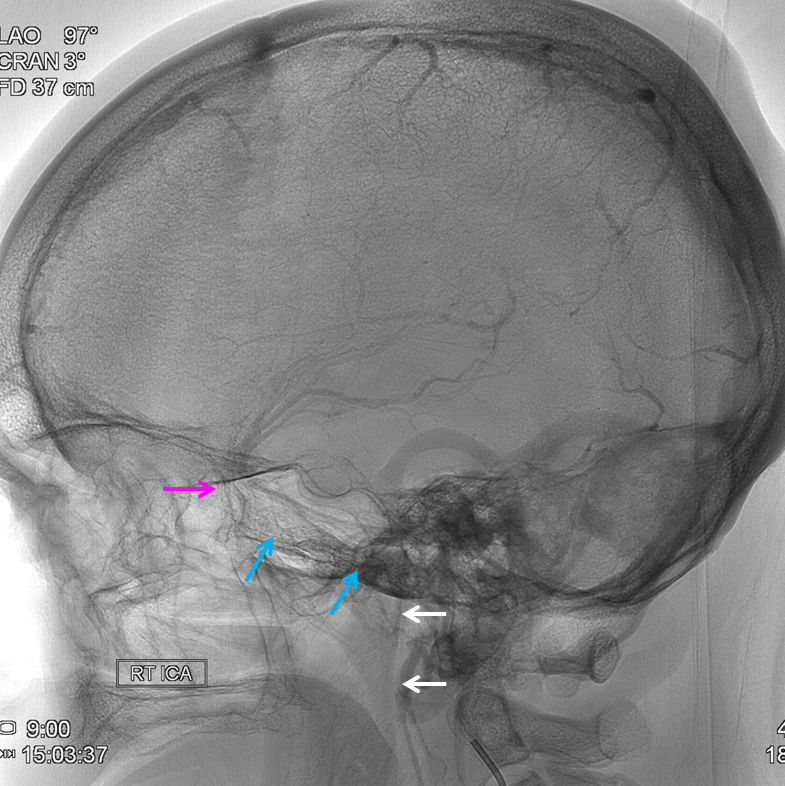

Sagittal Sinus Thrombosis — collaterals.

All of the above anatomic knowledge can become very useful in evaluation of venous thrombosis. Numerous collateral pathways develop in this setting attempting to compensate for the loss. The most dramatic cases usually involve the largest channel — the superior sagittal sinus. In this case, a man presented with what initially was thought to be vasculitis-related brain hemorrhage. Subsequent workup led to an angiogram, where sagittal sinus thrombosis with extensive trans-cerebral and trans-osseous emissary vein collateral channels was seen. In retrospect, these findings were present on the patient’s earlier contrast MRI. “Venovibe” or other contrast-enhanced MR venograms can very sensitive, particularly when interpreted with the appropriate index of suspicion. Noncontrast 2-D time of flight MRV I consider to be next to useless as a problem-solving technique. Any thin-slice postcontrast T1 study is vastly superior.